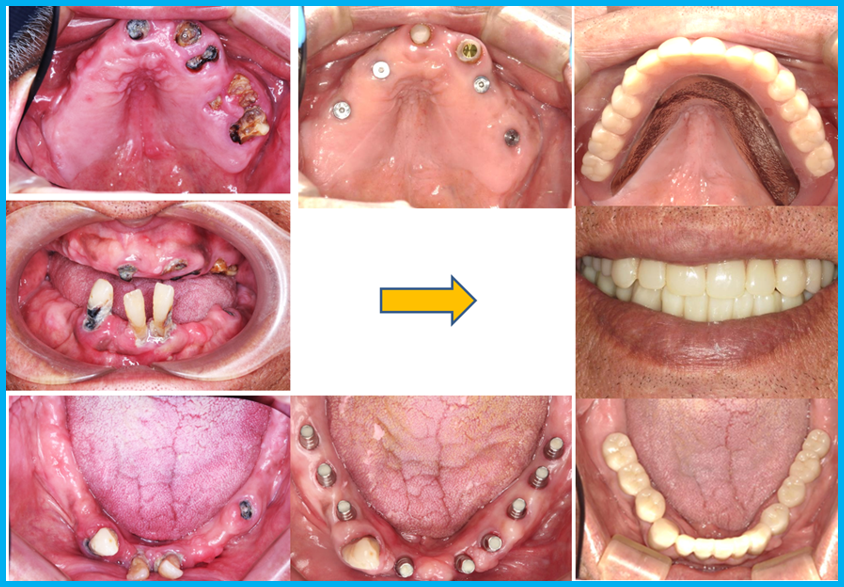

| 【主訴】 | 何を食べても食事が美味しくない。ただ美味しく食事を出来るようにだけになりたい。

| 【治療内容】 | 下顎はインプラントフルブリッジ、噛み合せが反対咬合、右側にずれる「かみ癖」のため、上顎はインプラント4本のオーバーデンチャー( 磁性アタッチメント義歯 )下顎は残存歯が1歯の多数歯欠損で手術用ガイドの固定源確保が困難でありましたが、インプラントをCTスキャンデータで作製した手術用ガイドを用いて9本埋入し、固定式3本連結のブリッジを3装置としました。

| 【治療期間・回数】 | 通院20回 、11ヵ月

| 【費用】 | 術前CT・診断29,700円/ガイデッドサージェリー91,300円/1次手術154,000円×13本、2次手術52,800円×13本/ブリッジ装着:前歯121,000円×6本,臼歯77,000円×6本/磁性アタッチメント55,000円×4・チタン床義歯264,000円、標準総額 380万円(税込)

| 【リスク・副作用】 | 手術後に炎症・痛み・腫れが生じる場合がありますが、下顎インプラントに関しましては、術前CTで血管・神経走向を確認して治療を進めるので、麻痺など症状が起こることはありません。